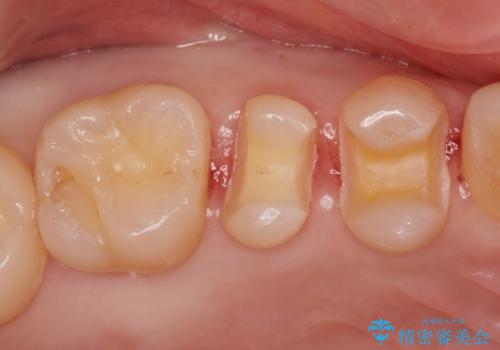

虫歯の再発リスクが高い樹脂修復部分をe-maxインレーに

- 歯と歯の間に古い樹脂の治療がされていて虫歯の再発のリスクが高まるためにe-maxインレー(セラミック)治療を行いました。

適合の良い詰め物が入りました。

セラミックは適合がよく虫歯の再発のリスクが低くなります。